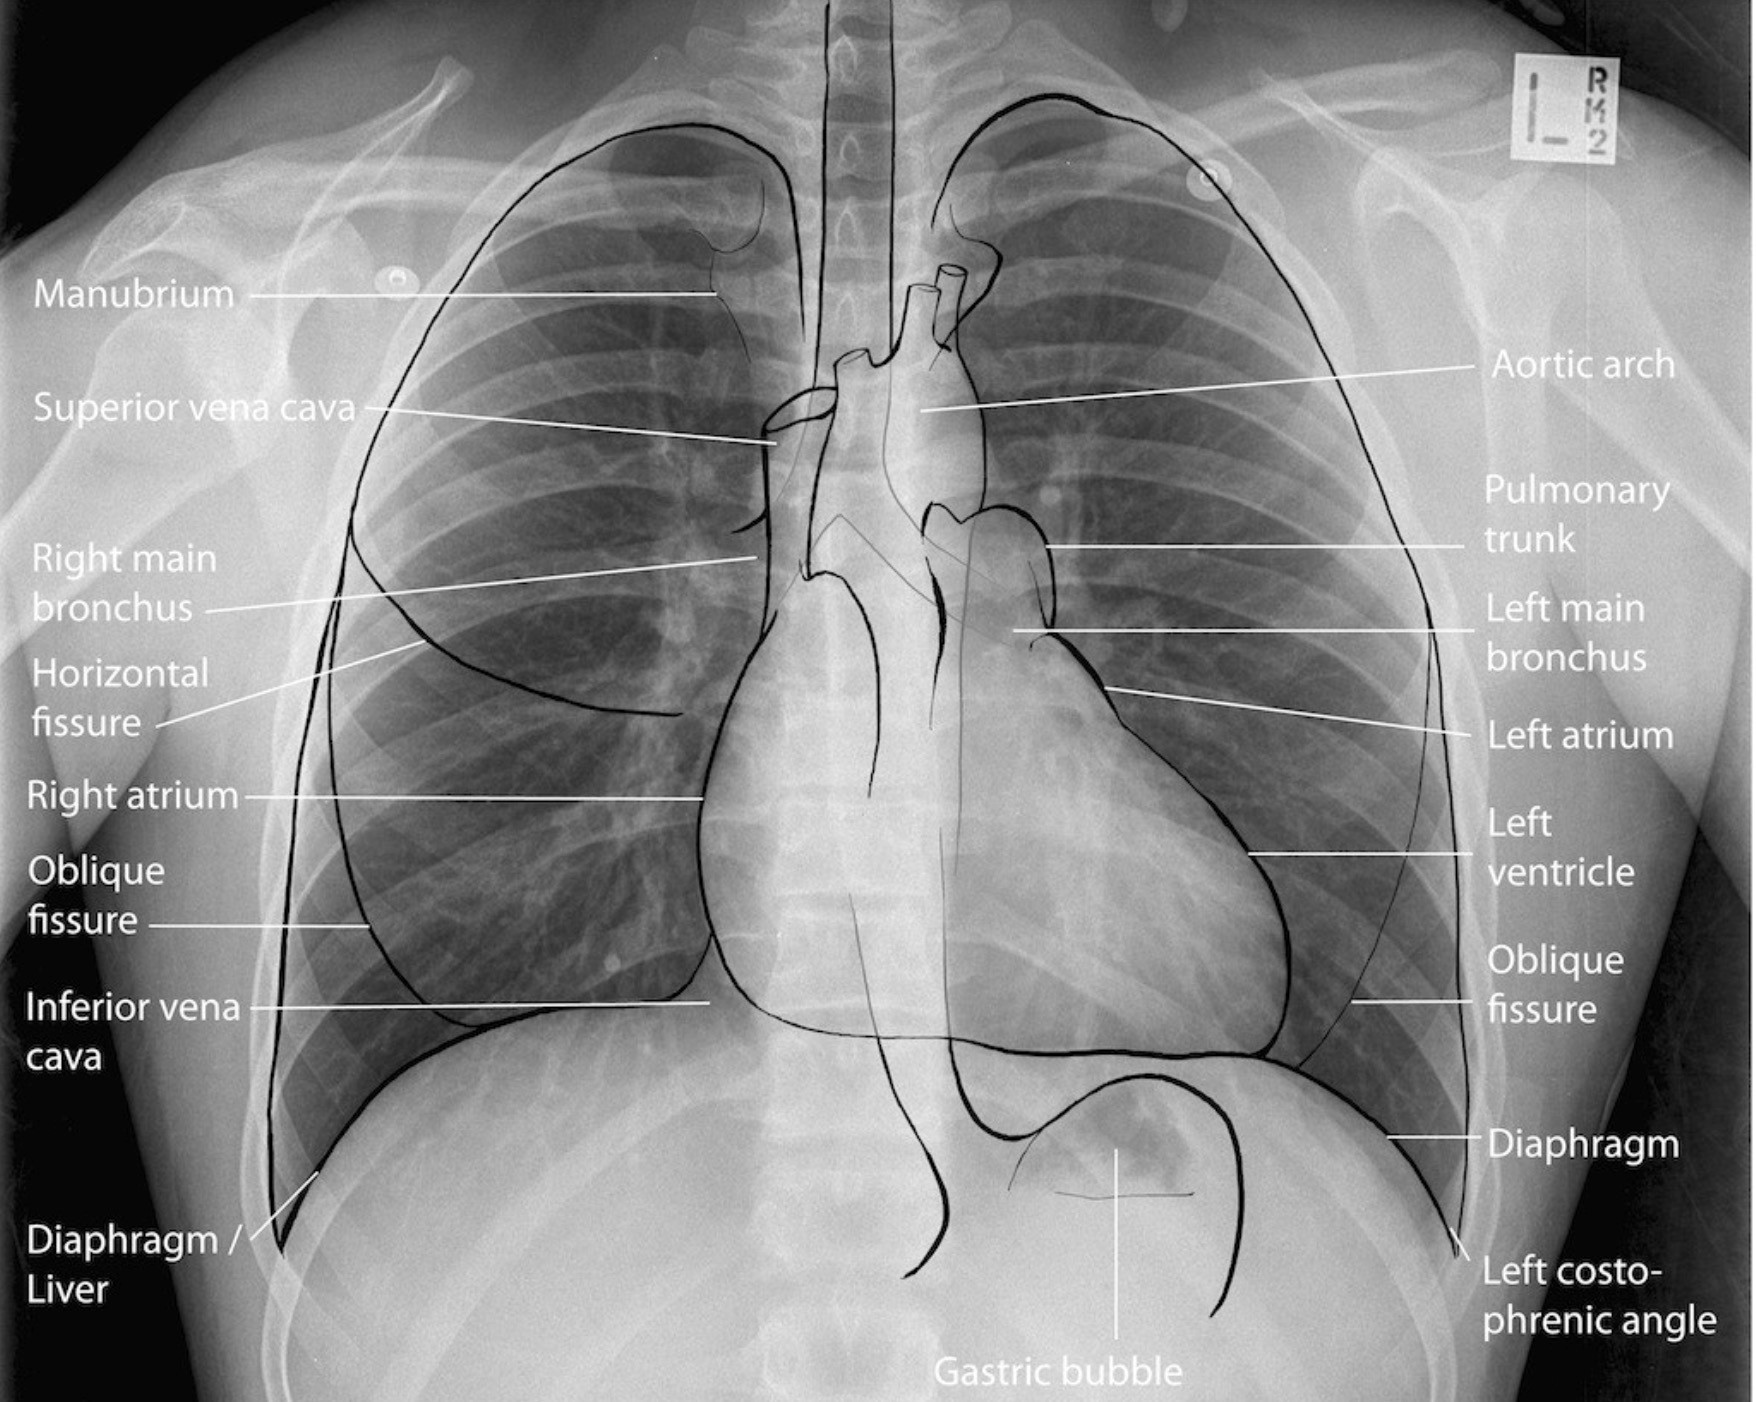

Анатомические изображения сегментов легких различных животных

Раздел: Другие животные